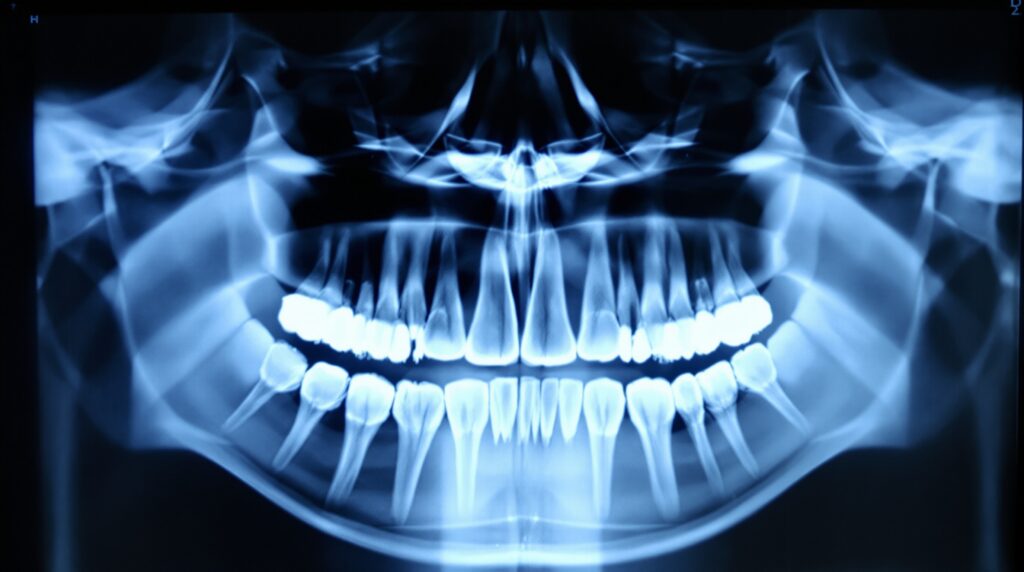

Panoramic radiography continues to serve as an essential screening tool for comprehensive oral assessment, providing broad coverage of dental and surrounding structures while maintaining relatively low radiation exposure.

The 2026 recommendations establish clear boundaries for CBCT imaging, emphasizing its use only when conventional 2D imaging proves insufficient. For orthodontic applications, panoramic radiography addresses many diagnostic needs, with CBCT reserved for complex cases requiring three-dimensional visualization.

CBCT offers superior resolution (75-200 μm) compared to traditional panoramic imaging (300-500 μm), making it invaluable for detecting fine anatomical details such as accessory canals and evaluating complex root morphology. However, the guidelines stress that this enhanced capability must be balanced against increased radiation exposure.

For orthodontic evaluation, the guidelines recommend starting with clinical examination and panoramic radiography. CBCT should be considered only when additional three-dimensional information will significantly impact treatment planning or when evaluating impacted teeth, root resorption, or airway assessment.